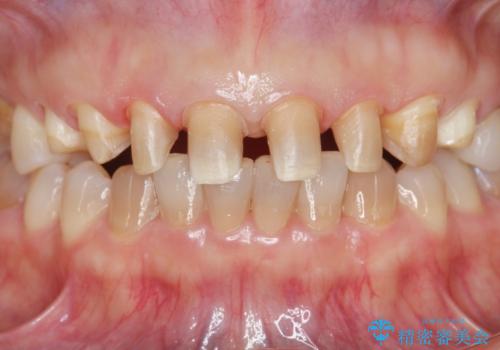

- 十数年前に行った、前歯のラミネートベニアの継ぎ目が見えるようになってきて見た目が気になる。

この際もう一度ラミネートでやり替えるのではなく、強度にも優れるクラウンにしたいと希望され来院されました。

ラミネートを丁寧に除去したのち、ジルコニアクラウンを作製し審美性の回復・向上を計画します。